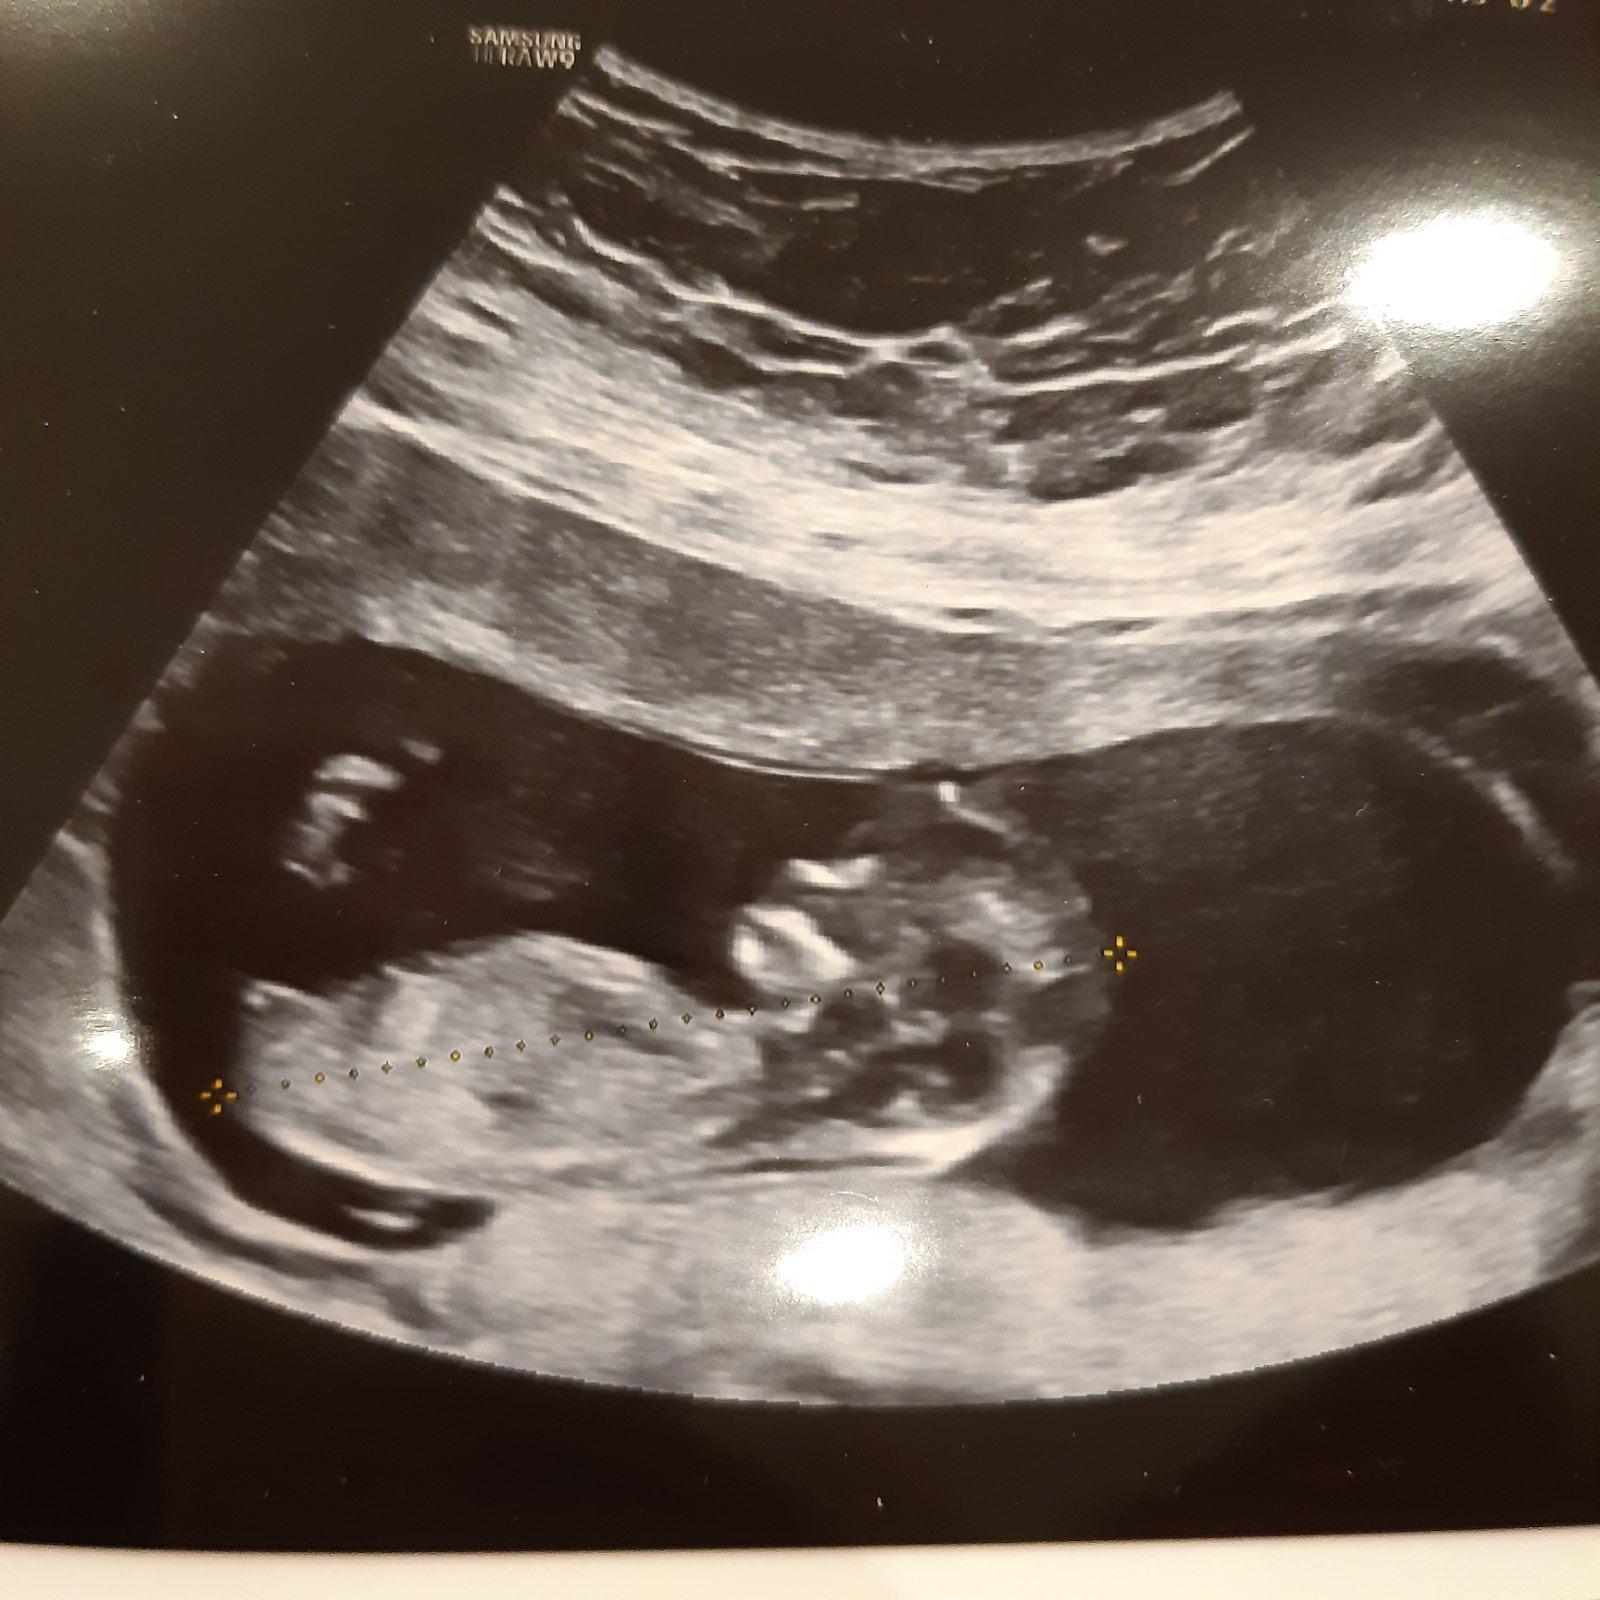

@sebinka123 tak už mám foto 😀 prý to vypadá na pátého kluka,ale zase to co vypadá jak pindík je nožka 😀 vidíš tu pohlaví? 😀

@juliemichal a co to tam mas zakrouzkovano?

@30bar to je asi mladší dvojče,mi říkaly 2 známé.jedna gynekoložka a druhá zdravotní sestra 😀 ale doufám,že ne-e

@juliemichal aha 🙂 tak to by to dvojce uz bylo asi vetsi. Jinak ten pohlavni hrbolek neni moc vidět. Neco tam trosku videt je a trci to spis nahoru,tak bych se klonila k chlapeckovi...touhu po holccice chápu...uvidis co ostatni holky

@30bar no doufám,že by bylo větší 😀 je tam právě druhý gestační váček,ale mě se zdá prázdný 😀

fakt?já tam právě ten pohlavní hrbolek nevidím 😀 asi jsem slepá 😀 tak bude pátý chlapeček 😀 😀

@juliemichal je, to je bobisek. Hele, tady fakt nic nevidím, pohlavní hrbolek je uz jakoby zakryty a ani podle čelního laloku to není moc poznat.

Výdrž zlato di toho 10.5, třeba bude lepší fotka.

A s tím dvojčetem to je jako fakt?